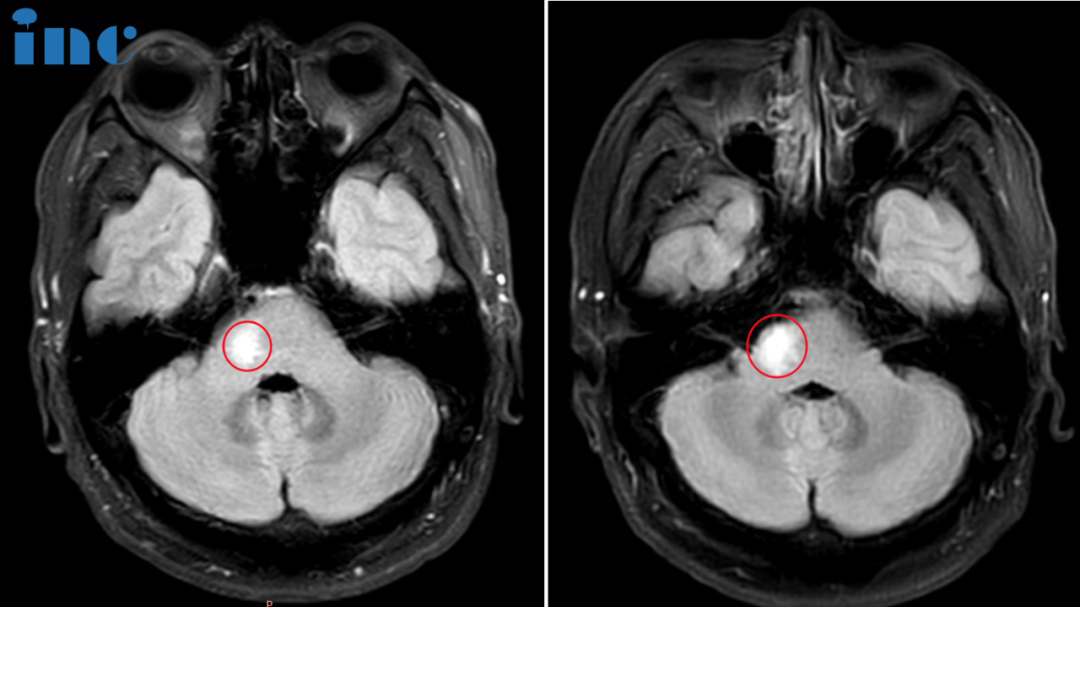

咨询室迎来2位患者,30岁的萱萱2023年3月查出中脑及桥脑右侧占位海绵状血管瘤继发出血。当地医生考虑手术风险大,偏瘫几率大,建议保守治疗。和很多年轻的脑干海绵状血管瘤女性患者一样,当她们步入婚姻自然的要迎接新的小生命。但这一直虎视眈眈的脑干海绵状血管瘤一旦伺机而动如出现急性脑干出血,而致患者和胎儿于困境中,又该怎么办?

萱萱多方打听之后,了解到在脑干海绵状血管瘤治疗领域一位国际神外教授巴特朗菲教授,专门研究过孕期海绵状血管瘤的治疗。通过INC他们远程咨询巴教授,巴教授表示这是一个潜在的手术病例,因为有相当大的内出血。然而,手术指征需仔细地被确定,因为这名年轻患者的临床状况好。我们较好在近期与患者单独面谈,详细讨论此事。得到巴教授的回复之后,他们决定再一次亲自见见巴教授,完全解决这个“不定时炸弹”。

详细问诊、审阅各种影像资料后,巴教授说道:“我有很多病人都患有这种畸形。通常,出过一次血,将来发生出血的可能性很高。而且这个畸形也不太小,至少有2厘米。这意味着,我们不能指望它可以一直保守下去。另一点是,如果你想要一个孩子,那么出血的风险也很高。这是众所周知的,这是因为怀孕后的激素。与正常情况相比,血液中的怀孕激素会增加更大的可能性。其中一些病变的表面有一个黄体酮的受体。黄体酮会导致新的出血。目前也没有药物可以治疗这个疾病,因此只能手术。这种手术是我的专长。我做过很多这样的手术,结果很好,没有长期性的问题。我在独墅湖医院做了很多手术,他们这里有很好的设施。切除率全切在海绵状瘤中,这是可能的。”